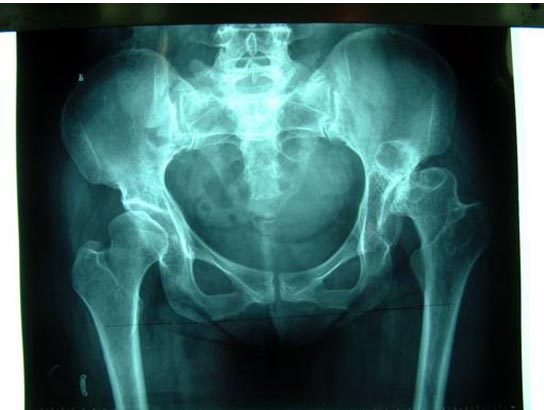

关节软骨破坏,关节间隙消失               股骨颈骨折,容易发生不愈合